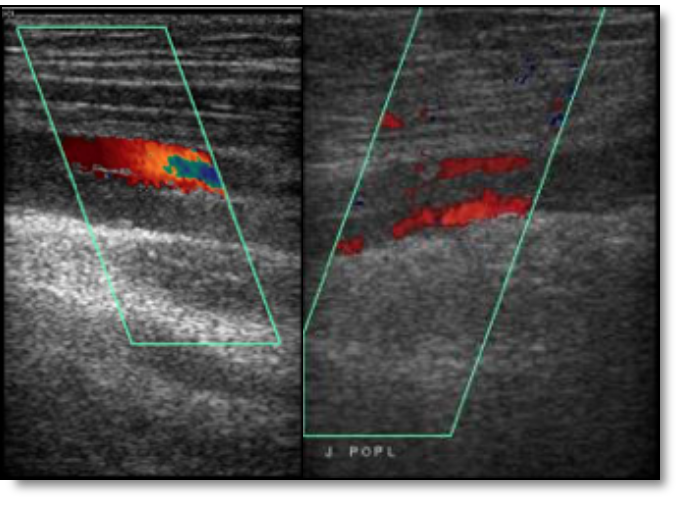

6 héttel a kezelés megkezdése után jobb alsó végtagi fájdalmat érzett, a fizikális vizsgálatkor enyhe fokú körfogatdifferenciát lehetett tapasztalni, a Homans-tünet pozitív volt. A color Doppler UH. vizsgálat a jobb v.femoralis supeficialis teljes, a poplitea részleges elzáródását mutatta. A rosszabbodó általános állapota, fokozódó nehézlégzése miatt intenzív osztályra helyezték át.